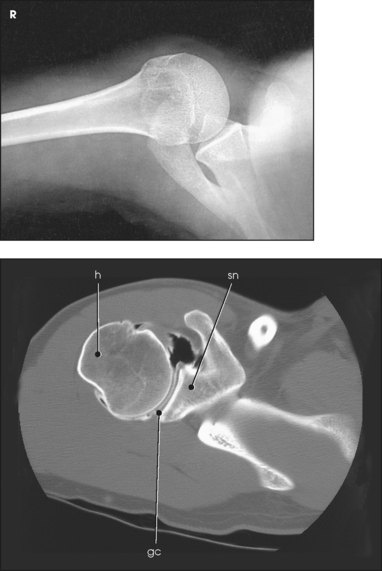

The scapulohumeral articulation between the glenoid cavity and the head of the humerus forms a synovial ball-and-socket joint, allowing movement in all directions (Figs. 5-9 and 5-10). This joint is often referred to as the glenohumeral joint. Although many muscles connect with, support, and enter into the function of the shoulder joint, radiographers are chiefly concerned with the insertion points of the short rotator cuff muscles (Fig. 5-11). The insertion points of these muscles—the subscapular, supraspinatus, infraspinatus, and teres minor—have already been described.

Fig. 5-10 A, Coronal MRI of shoulder. Note articular cartilage around humeral head and muscles closely surrounding bone. B, Axial CT of shoulder, mid-joint. Note position of bones relative to each other and articular cartilage in glenoid cavity. gc, glenoid cavity; h, humerus; sn, scapular neck. (From Kelley LL, Petersen CM: Sectional anatomy for imaging professionals, ed 2, St Louis, 2007, Mosby.)